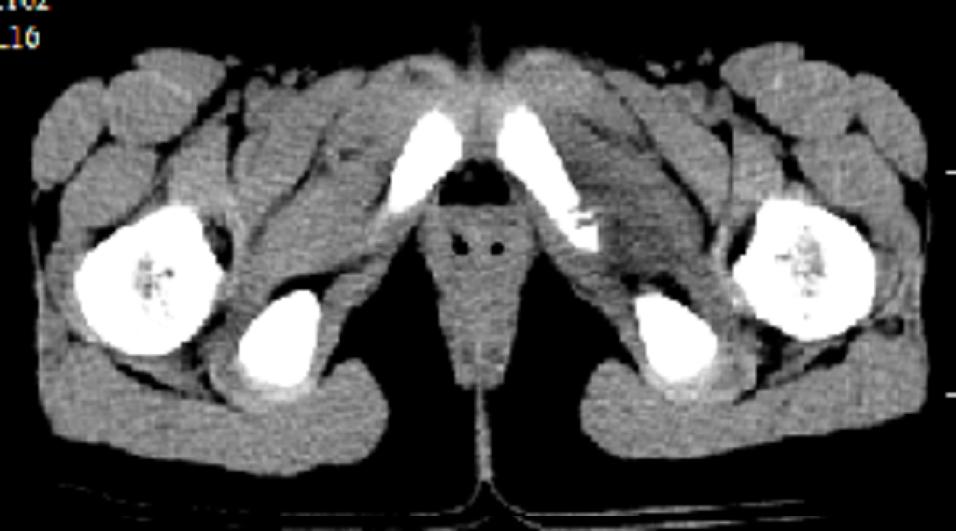

以下是引用dyqct在2008-7-2 15:38:00的发言:[br]左坐骨与耻骨交界处膨胀性溶骨性病变,周围软组织略肿胀,边界不清。[br]发生在这个年龄组该部位最常见的一种发育变异,可以出现此种改变。另外感染不除外,建议定期复查。